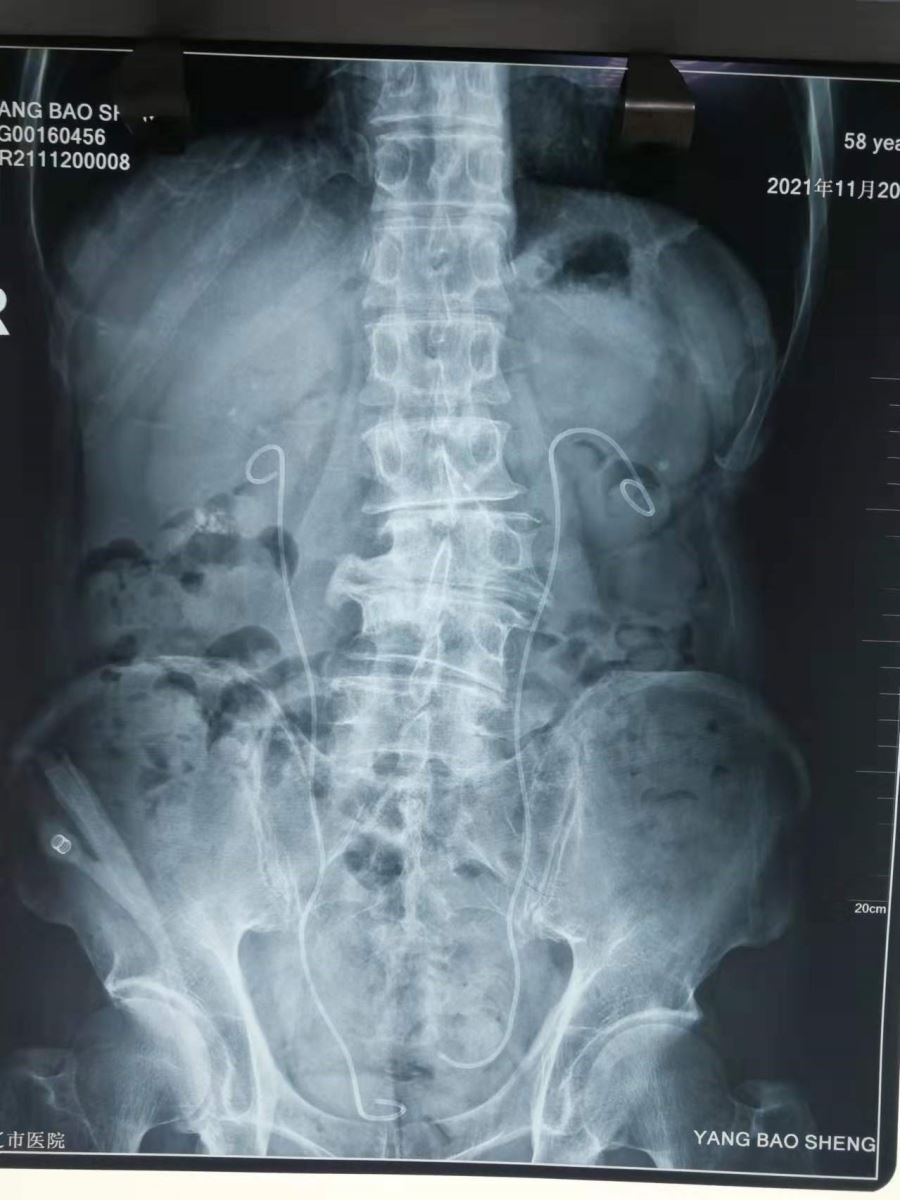

患者杨某,男,58岁,入院40天前经彩超检查发现巨大右肾铸形结石、左肾多发结石。曾前往市内、外多家医院就诊,因结石过于巨大和复杂,均未接诊,此次慕名来我院泌尿外科求治。经完善检查,充分术前准备,先期处理了肾积水较为严重的左肾多发结石,两周后为右肾实施手术,手术历时2个小时十分钟,顺利取出粉末化的结石,复查无明显结石残留。目前,患者在泌尿外科医护人员的精心呵护下已经痊愈出院。

术后影像